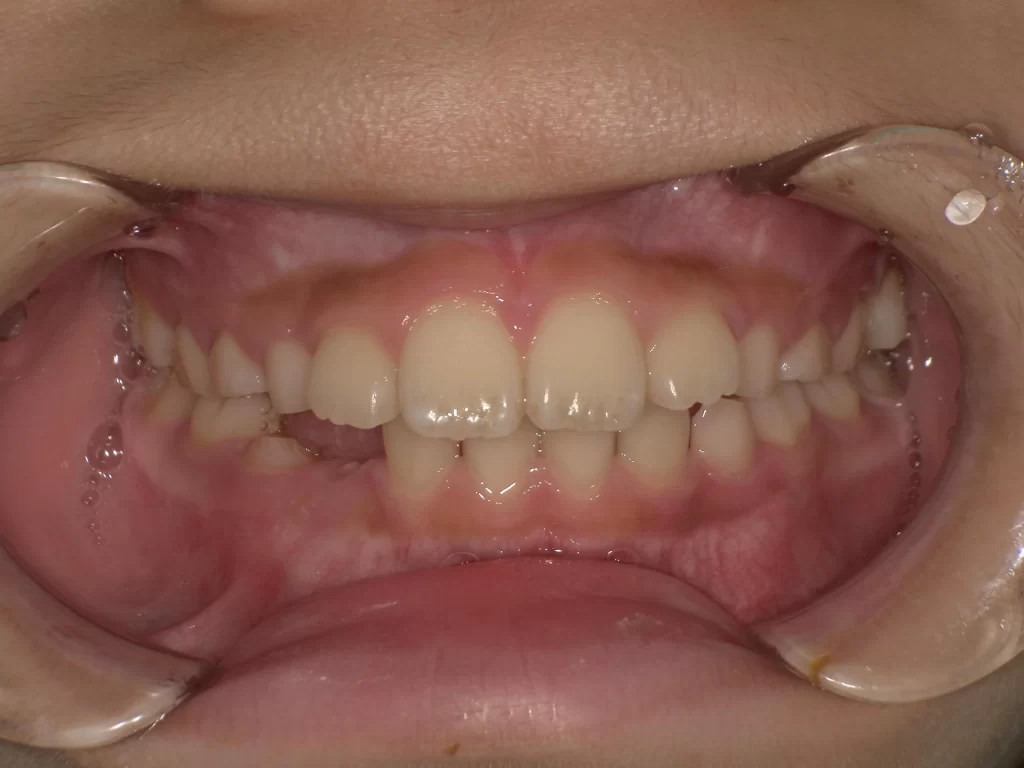

症例④:10歳・出っ歯・深い噛み合わせ

【使用期間:3ヶ月】

上の前歯が出ていることと、下の歯が見えなくなるほど噛み合わせが深い(過蓋咬合)ケースです。

▼ 治療前(Before)

▼ 使用3ヶ月後(After)

- 年齢・症状: 10歳、上顎前突、過蓋咬合

- 治療法: プレオルソ

- 期間: 3ヶ月

- 結果: たった3ヶ月の使用で、出っ歯感が減り、深すぎた噛み合わせが正常な位置に改善されました。